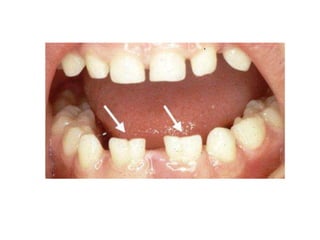

8. Gemination

Merupakan anomali yang terjadi ketika satu

tooth bud berusaha untuk membelah.